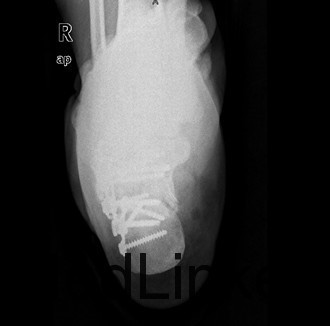

患者男,37岁,因“外伤后双足跟疼痛、肿胀伴腰痛11+天”入院。患者11+天前和工友施工时不慎从二楼摔下,双足跟着地,当时即感双足剧烈疼痛,踝关节活动障碍,伴腰背部疼痛,左足跟长约3厘米伤口,患者诉可见骨断端外露,伤后2小时患者被送往当地人民医院,急诊行清创缝合术,术后给予输液、抗炎、消肿等对症治疗,双足水肿减轻,患者为求诊治进一步诊治来我院,急诊以双足跟骨折收住我科。

查体:双足中度肿胀,左足跟底内侧长约3cm清创缝合术后伤口,伤口干燥,无红肿渗液,双足背、足底、双踝关节中度肿胀,双足皮温正常,足背动脉正常扪及,双下肢肌力五级,双足趾活动正常,双踝关节疼痛活动受限。 辅查:双足X线示:双足跟粉碎性骨折,关节面塌陷。

初步诊断:1、右跟骨粉碎性骨折2、左跟骨粉碎性开放性骨折清创缝合术后 诊疗计划:拟行双侧跟骨切开复位植骨、钢板、螺钉内固定术+髂骨取骨术